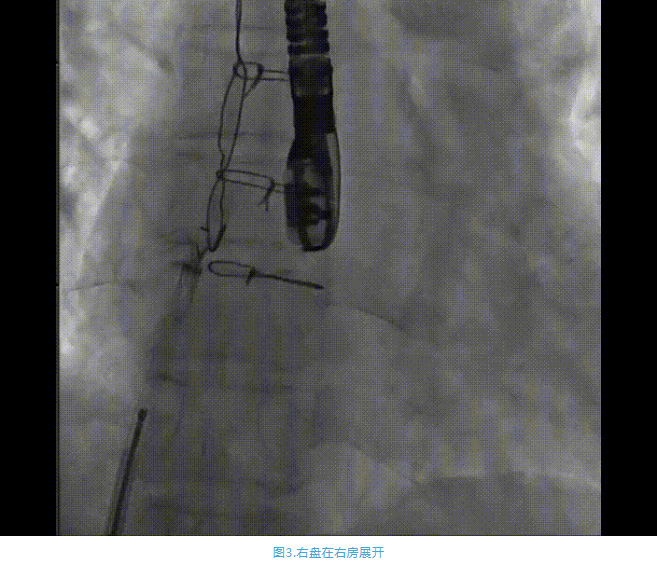

術(shù)中首先在局麻下穿刺股動脈、股靜脈,完成心導(dǎo)管檢查評估后轉(zhuǎn)為全麻,在食道超聲引導(dǎo)下穿刺房間隔,穿刺成功后將加硬導(dǎo)絲送入左上肺靜脈建立軌道,根據(jù)患者病情行球囊預(yù)擴(kuò)張后植入6mm孔徑房間隔造孔支架,經(jīng)透視及食道超聲評估支架左右盤展開良好,夾持于房間隔兩側(cè),固定穩(wěn)定、位置良好,食道彩超顯示房水平右向左為主分流,分流孔直徑符合預(yù)期大小,心導(dǎo)管檢查評估達(dá)到預(yù)期效果,釋放造孔支架。術(shù)后12h患者下床活動,恢復(fù)順利,擬于近日完善術(shù)后評估后出院。